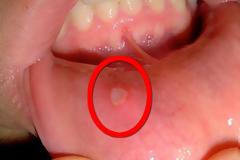

Άφθα, επώδυνη πληγή στο στόμα. Τι να κάνετε με τις άφθες;

Γιώργου Κουτσικάκη Dr. Μ. Sc http://www. dentistpefki. gr Συντάκτης Γιώργος Κουτσικάκης Χειρουργός Οδοντίατρος Μ